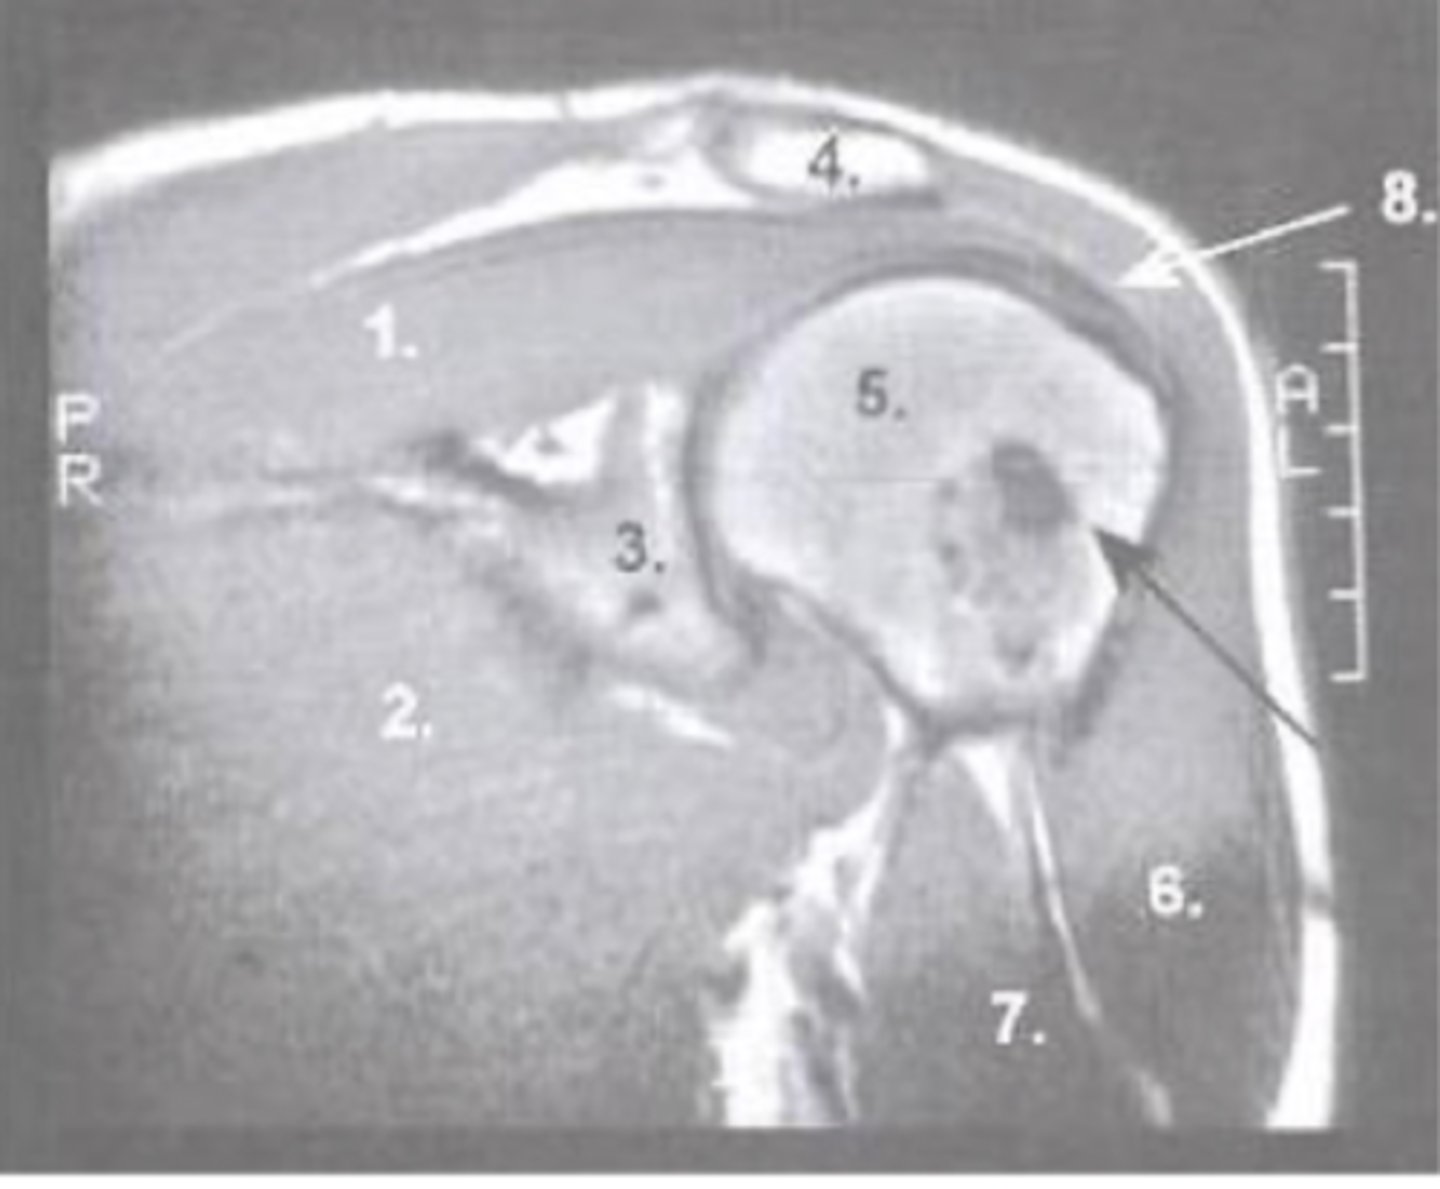

Supraspinatus muscle

What is number 1?

Pec major

What is number 2?

Glenoid

What is number 3?

Acromion

What is number 4?

Humeral Head

What is number 5?

Deltoid

What is number 6?

Biceps Long Head

What is number 7?